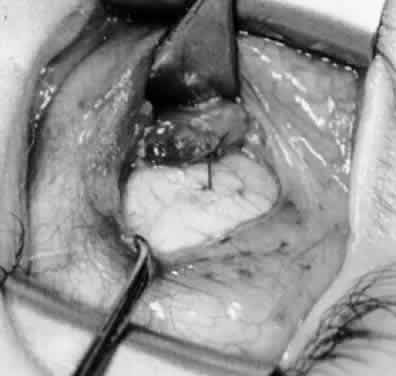

Fig. 28. The inferior oblique muscle is drawn further into the operative field, and a 3-0 Vicryl suture ligature is applied about the belly of the muscle.

Fig. 29. Cautery is used to sever the inferior oblique muscle and to provide hemostasis.

Fig. 30. The stump of muscle is placed through the Tenon's capsule opening. The surgeon must apply sufficient cautery to prevent postoperative bleeding.

Fig. 31. The inferior oblique muscle stump is visible at the opening in the Tenon's capsule before closure with 6-0 or 7-0 Vicryl suture. The S-28 half-circle curved needle is preferred to the S-29 needle, which has a 3–8-circle curve.

Fig. 32. The Tenon's capsule opening is closed with 6-0 or 7-0 Vicryl suture to place the inferior oblique muscle entirely outside Tenon's capsule.